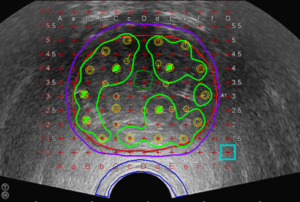

Die untenstehenden Grafiken zeigen folgendes:

A: Radioaktives Stäbchen (Seed)

B: Das Röntgenbild des Beckens zeigt die implantierten Stäbchen (Seeds)

C: Bestrahlungsplanung einer Prostata